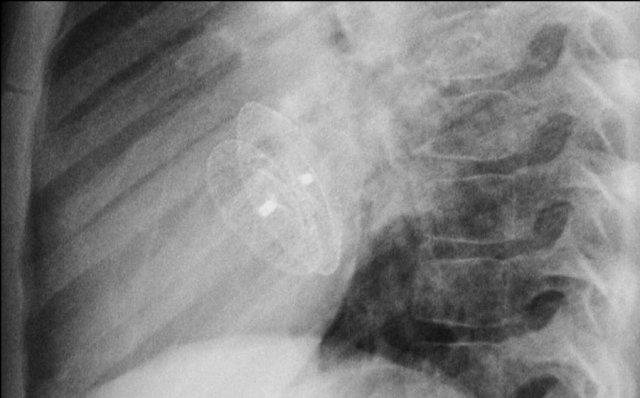

Hình ảnh được chụp ngay sau khi đặt ICD.

Có hình ảnh tràn khí màng phổi nhỏ (mũi tên).

Đây là biến chứng thường gặp nhất.

Đây là bệnh nhân có ICD với một điện cực và hai cuộn sốc điện.

Có thể thấy điện cực lưu lại của máy tạo nhịp cũ đã được tháo bỏ.

Nhiều bệnh nhân có điện cực máy tạo nhịp nội tâm mạc được để lại sau khi tháo bộ phát xung.

Tính an toàn của MRI ở bệnh nhân có điện cực máy tạo nhịp nội tâm mạc lưu lại cho đến nay vẫn chưa được nghiên cứu một cách hệ thống.

Tuy nhiên, do nguy cơ tiềm ẩn khi các điện cực này có thể hoạt động như “ăng-ten” gây nóng đáng kể – không khuyến cáo chụp MRI cho những bệnh nhân này (tài liệu tham khảo).